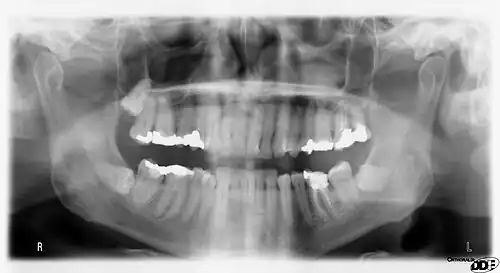

Arrows point to two vertical white lines which is how calcifications in the first part (proximal component) of the internal carotid artery appear on panoramic radiographs.

Panoramic radiographs have the capability to demonstrate a portion of the neck and display atheromas (calcifications in the carotid artery) which are an indication of both local and generalized (systemic) atherosclerosis. Atherosclerosis of the coronary arteries leading to myocardial infarction (heart attack), and atherosclerosis of the carotid artery leading to stroke are the number one and number three most common causes of death in the United States.[6]

There is interest to look at panoramic radiographs as a screening tool, however further data is needed with regards if it is able to make a meaningful difference in outcomes.[7]

Epidemiology: general public and high risk groups

Additional research projects have further determined the prevalence rate of these atheromas in the general population (3–5%)[8][9] and among high-risk groups (over 25% in: recent stroke victims,[10] individuals with obstructive sleep apnea syndrome,[11][12][13] postmenopausal women,[14] type 2 diabetics,[15][13][16] individuals with dilated cardiomyopathy,[17][13] and among individuals who have received radiotherapy directed at the neck,[18][19]). These findings have been corroborated by other several other researchers.[20][21][22][23][13]